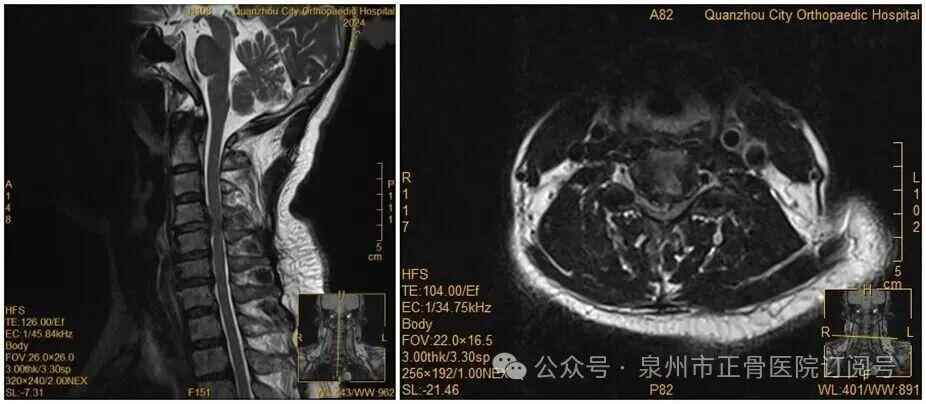

王女士术前MRI

此前,她因手麻、酸痛到医院就诊,被查出颈椎间盘突出症罗瑟汉姆 vs 保顿艾尔宾 。脊柱二科杨声坪主治医师回忆:“会诊时我们明确告知患者,她的颈椎间盘已经巨大脱出,符合手术指征,建议尽快手术。但她坚持想保守治疗。”

没想到,会诊当晚,王女士翻身拿手机的瞬间,双手突然失去知觉——关键肌肌力降至1级或0级,确诊为瘫痪罗瑟汉姆 vs 保顿艾尔宾 。“推测是翻身时,脱出的椎间盘突然进一步卡压到脊髓神经,引发了急性症状。”医生表示。